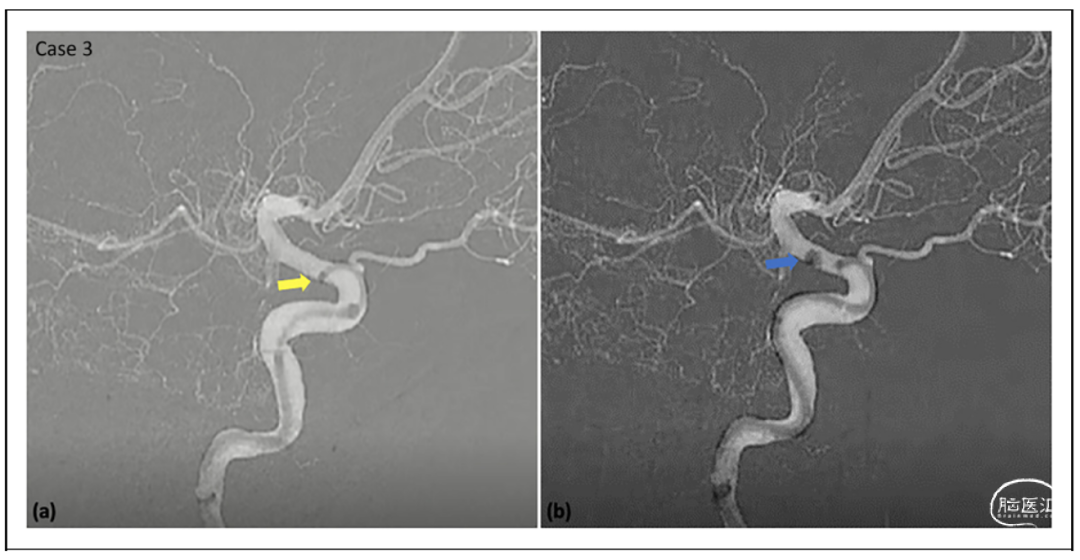

结果

病例集锦